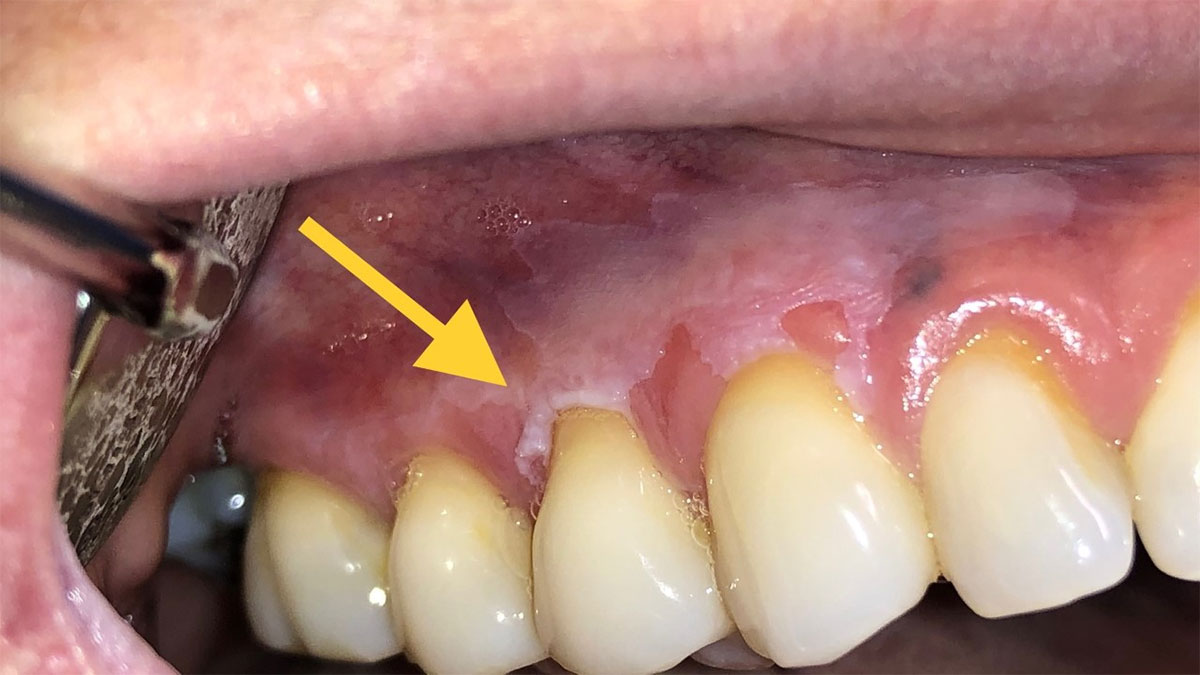

ضایعات پیش بدخیم دهان و روشهای درمان آنضایعات پیش بدخیم دهان مانند لکوپلاکیا و اریتروپلاکیا می توانند به سرطان تبدیل شوند. با علل ایجاد این ضایعات و درمان نوین آنها با لیزر آشنا شوید. ...